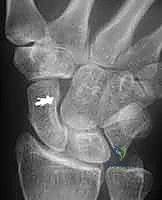

Radiographs, while not always definitive in early stages, provide crucial information.

* PA View: We look for a scapholunate gap >3mm or wider than the contralateral side, and the cortical "ring" sign.

* AP View (Clenched-fist): This view accentuates the scapholunate gap by applying axial load.

FIG 2 • A. Clenched-fist PA view with the wrist in supination, demonstrating a significant increase in the scapholunate interval space.